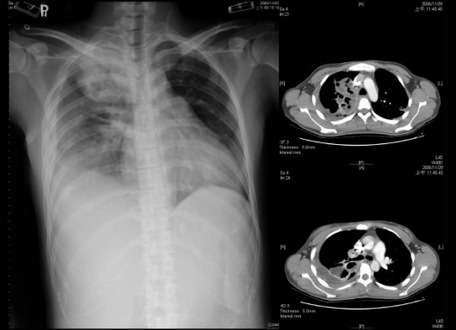

An empyema (/ˌɛmpˈmə/) is a collection of pus within a naturally existing anatomical cavity. For example, pleural empyema is empyema of the pleural cavity. It must be differentiated from an abscess, which is a collection of pus in a newly formed cavity. The term is from Greek ἐμπύημα, "abscess".

Lungs[edit | edit source]